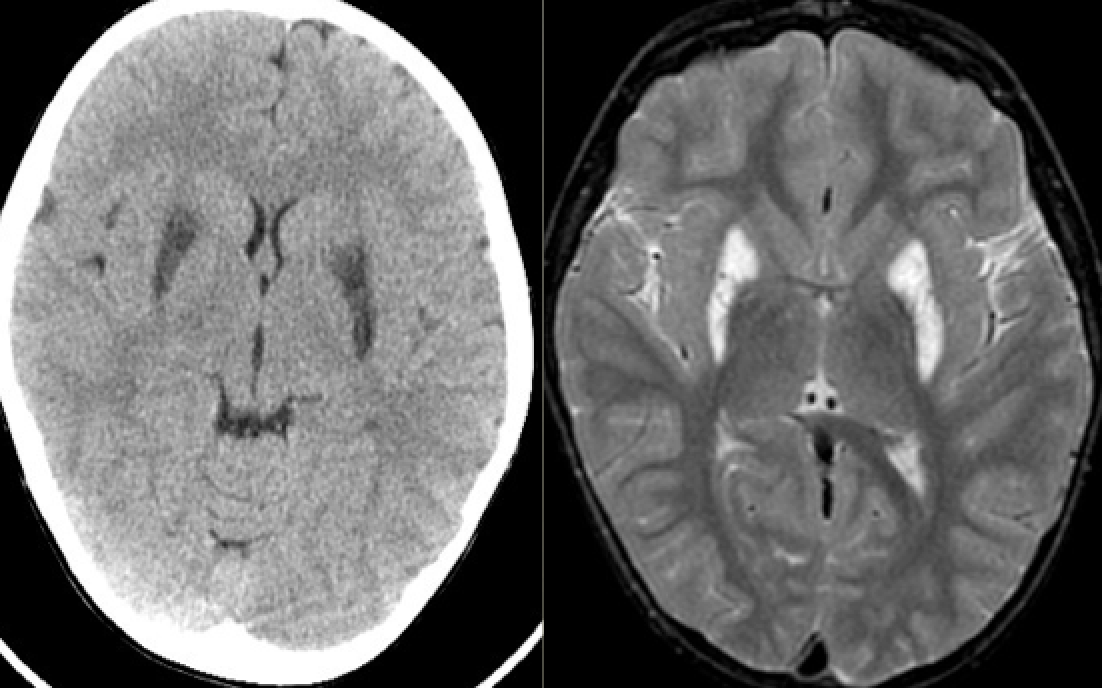

15 month old boy with progressive loss of milestones

Diagnosis, Genetics, Clinical features, and Treatment?

Other differential diagnoses?

Leigh disease (subacute necrotizing encephalomyelopathy)

Mitochondrial disorder, due to nuclear (autosomal or X-linked) or mito DNA mutations affecting oxidative phosphorylation (ex. pyruvate dehydrogenase, pyruvate decarboxylase, or cytochrome C oxidase)

Clinical features: Lactic acidosis, hypotonia, ophthalmoparesis, cardiomyopathy

Treatment: Bicarb/citrate, thiamine, ketogenic diet

CT: Hypodense basal ganglia

MRI: T2 hyperintense basal ganglia (GP/putamen/caudate)

MRS: reduced NAA, elevated lactate

Can look similar to Wernicke’s but spares mammillary bodies and red nuclei

Other differential diagnoses:

methanol and Wilson’s: T2 hyperintensities in putamen

carbon monoxide and cyanide poisoning: T2 hyperintensities in globus pallidus

Kearn-Sayne syndrome

(thanks fo Raf Llinas)